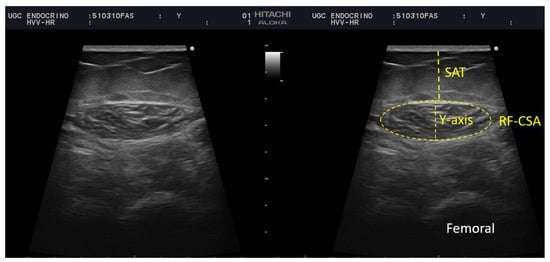

Rectus Femoris (RF) Ultrasound Assessment

| Cross-sectional area (cm2) | 4.35 (3.5–5.33) | 4.76 (3.56–5.43) | 3.65 (2.80–3.89) | 0.025 | |

| Muscle circumference | 9.43 (8.53–10.15) | 9.54 (8.73–10.30) | 8.61 (7.55–9.83) | 0.096 | |

| Muscle thickness (Y-axis) | 1.38 (1.15–1.61) | 1.40 (1.15–1.63) | 1.22 (0.87–1.60) | 0.564 | |

| X-axis | 3.95 (3.35–4.24) | 3.99 (3.66–4.24) | 3.28 (2.69–4.48) | 0.266 | |